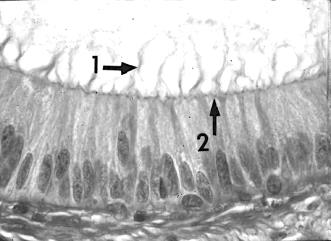

QCM 35 : A propos de cette photo, de quelle type d’épithélium s’agit t’il ?

A) Cylindrique pseudostratifié

B) Cubique pseudostratifié

C) Pavimenteux pluristratifié

D) Prismatique pseudostratifié

E) Les propositions A, B, C et D sont fausses

Réponse : AD !!